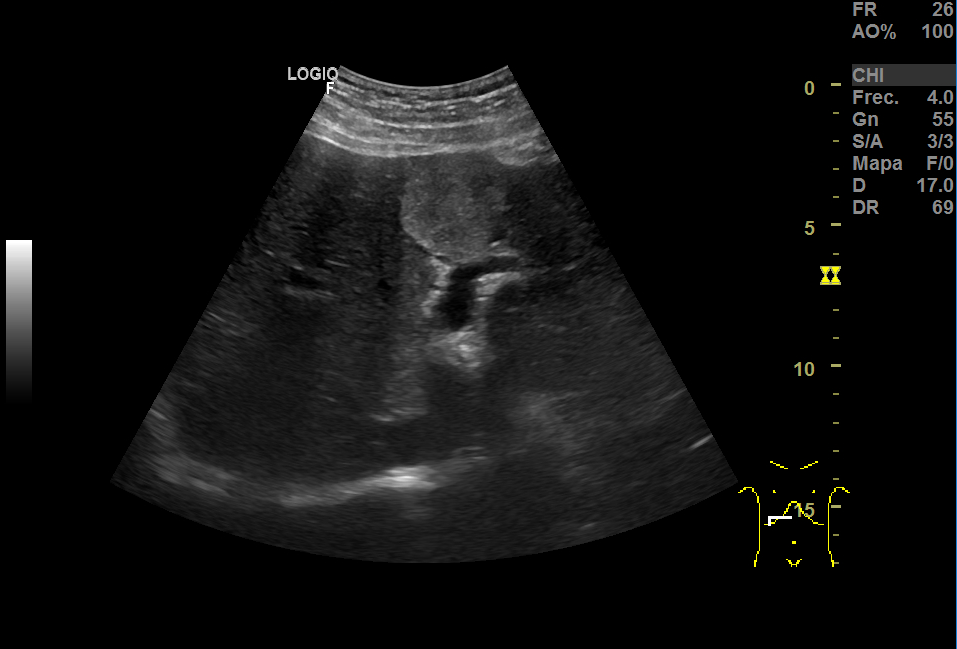

En la ecografía, a nivel hepático, vimos unas imágenes hiperecoicas redondeadas hipervascularizadas: una de aproximadamente 5 cm de diámetro y otra de 3cm, sospechosas de LOEs (lesiones ocupantes de espacio).

Repite la ecografia: En el segmento IV, aparece una imagen redondeada de 30x40 mm heterogénea, iso-hipoecogénica sin captación ecodoppler que podría ser un angioma, HFN (hiperplasia nodular focal) u otra posibilidad; otra imagen oval hiperecogénica de 19 mm, que sugiere angioma como primera posibilidad.

TAC con contraste: Se ven al menos cuatro lesiones hipodensas, con realce centrípeto compatible con hemangioma.

El aspecto de los hemangiomas hepáticos en la ecografía son lesiones de pequeño tamaño (inferior a 30 mm), hiperecoicas, bien delimitadas, homogéneas, con refuerzo acústico posterior y sin captación en el estudio Doppler. En cambio, el aspecto ecográfico atípico como el de nuestro caso: mayor tamaño, heteroecoico con zona central hipoecoica y límites irregulares o mal definidos, requiere de otras técnicas.